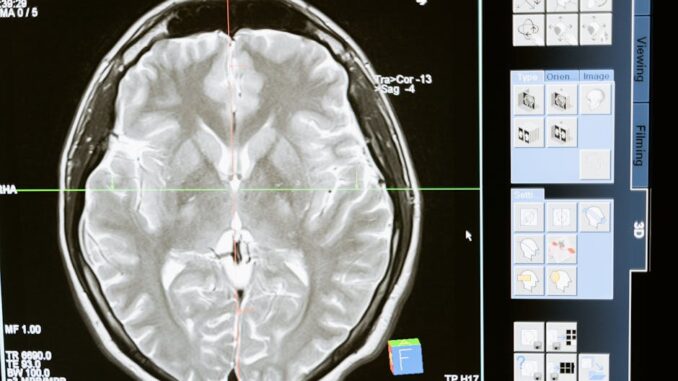

3.3 Neurology: Mapping the Brain’s Complexity

Hybrid imaging systems are pivotal in neuroscience, providing unparalleled insights into neurodegenerative disorders, brain tumors, epilepsy, and other neurological conditions.

3.3.1 PET–MRI in Neurology

PET–MRI is especially suited for neurological applications due to MRI’s exquisite anatomical detail of the brain and PET’s ability to map specific neurochemical and metabolic processes. (ajronline.org)

- Brain Tumors: MRI is essential for characterizing brain tumors. Integrating PET (e.g., FDG for glucose metabolism, C-11 Methionine or F-18 FET for amino acid transport) enhances tumor grading, delineates tumor margins more accurately, distinguishes recurrence from treatment-related necrosis (pseudo-progression), and identifies areas for targeted biopsy. Multi-parametric MRI (perfusion, DWI, spectroscopy) further enriches the data.

- Epilepsy: PET–MRI is invaluable for pre-surgical evaluation of intractable epilepsy. Interictal FDG PET often reveals areas of hypometabolism corresponding to the epileptogenic focus. MRI provides high-resolution anatomical imaging to detect subtle structural lesions (e.g., focal cortical dysplasia, hippocampal sclerosis). Fusing these data sets helps precisely localize the seizure onset zone, guiding surgical resection and improving outcomes.